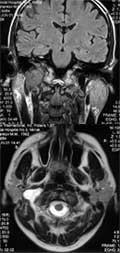

В отличие от гломусных опухолей, которые растут в латеральных отделах яремного отверстия и приводят к описанным выше изменениям костных структур, злокачественные новообразования в этой области чаще растут медиально, вызывая деструкцию затылочной кости и кливуса. При гломусных опухолях маленьких размеров, не приводящих к деструкции костных структур, целесообразнее проводить МРТ в аксиальной и коронарной проекциях. Характерным для гломусных опухолей является их связь с луковицей яремной вены (Рис. 3).

[Увеличить]

Рис. 3. МРТ. Опухоль яремного отверстия справа.